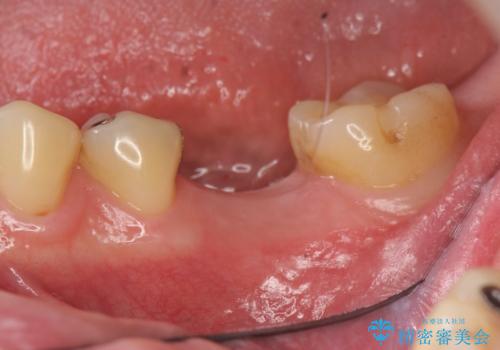

銀歯・レジンコアを除去したところ、薄い残存歯質に亀裂が入り、保存が難しい状況が認められました。

歯を残すことが難しい状況であることの説明、抜歯の提案を行い、抜歯後はブリッジ・入れ歯ではなくインプラント治療を希望されました。